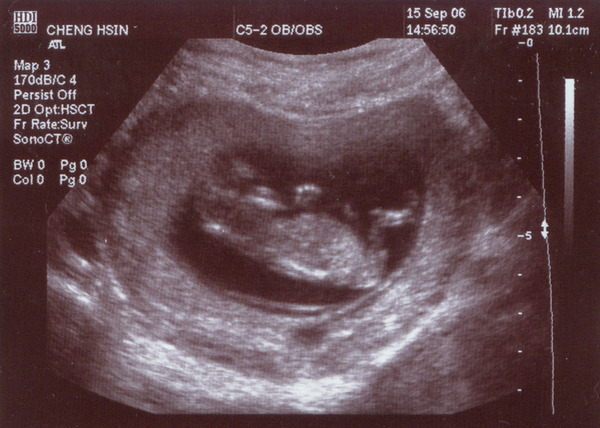

• [0d] Violet的第一篇

Violet是媽媽肚子裡小貝比的英文名字,媽媽超喜歡的,就先取了。

12週的相片:

已經5公分多囉

身體清晰可見

頸後透明帶厚度正常

鼻骨正常 (比較不易為唐式症兒)

手指、腳指數目也正常

(以上都是醫師說的啦,我什麼也看不懂)